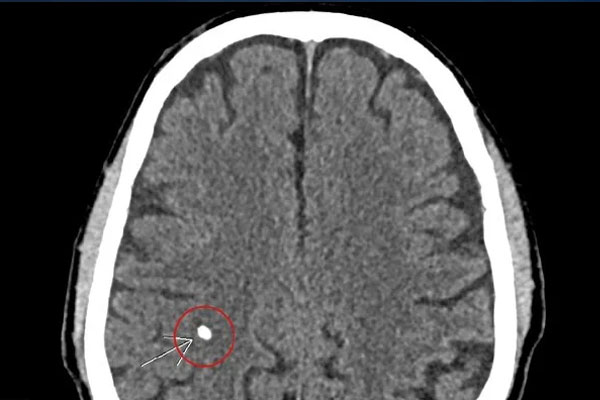

Nhu mô não có hình ảnh rải rác các di chứng ấu trùng sán não, kèm theo tổn thương viêm đa xoang, xơ vữa vôi hoá động mạch cảnh hai bên đoạn xoang hang.

Chuyên gia nhận định đây là trường hợp tuyến giáp to bất thường hiếm gặp, kèm theo di chứng sán não nên giải thích và tư vấn cho người bệnh lên tuyến trên điều trị kịp thời tránh những biến chứng xấu ảnh hưởng thêm tới sức khỏe.